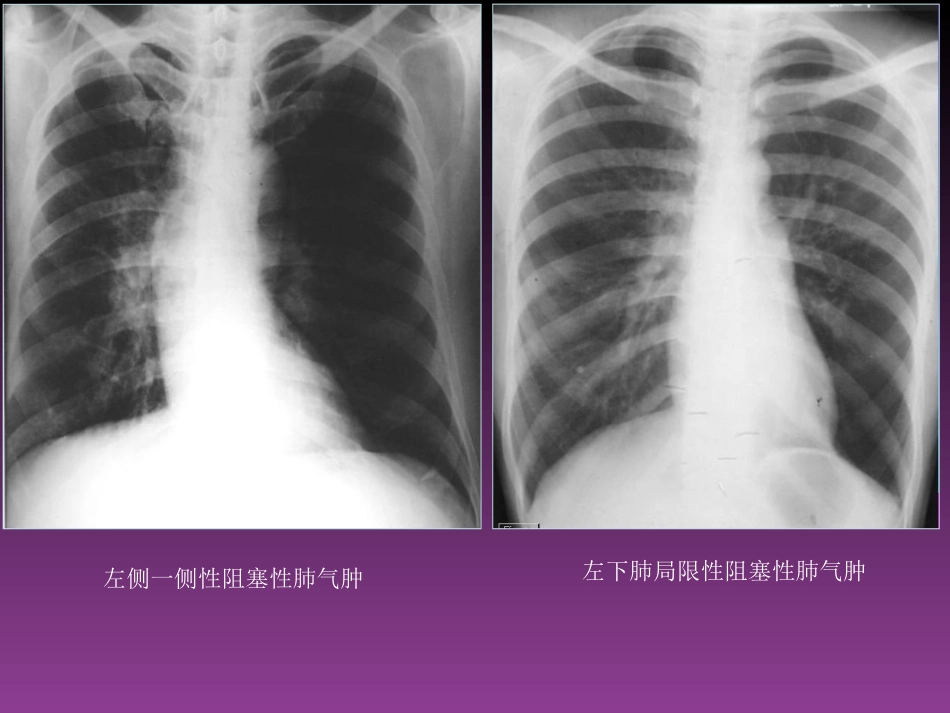

呼吸系统基本病变的X线表现X线征象(表现)--基本病变--病变性质--疾病诊断临床诊断:临床表现(病史、体检等)--一种、几种可能的诊断;影像资料等各种辅助检查--验证或否定、排除影像诊断:影像征象--病理基础--疾病可能;结合临床表现--最合理的解释(一)支气管改变病因,常规X线主要为肺的间接表现1.阻塞性肺气肿--活塞机制(1)局限性左侧一侧性阻塞性肺气肿左下肺局限性阻塞性肺气肿代偿性肺气肿(2)弥漫性肺气肿2.阻塞性肺不张--完全阻塞,肺外压迫,肺内疤痕收缩;一侧性,肺叶,肺段,肺小叶;右上叶不张右下叶不张左下叶不张右中叶不张一侧性肺不张右上中央型肺癌(二)肺部病变1.渗出与实变定义、病理X线表现全肺叶实变SARS肺水肿支气管气像(airbronchogram)支气管气像(airbronchogram)各种实变:云雾、云絮、斑片、大片、团片2.增殖与腺泡结节定义、病理及X线表现浸润型肺结核中的渗出、增殖和干酪坏死病灶3.纤维化(实质、间质)定义、病理及X线表现4.钙化定义、病理及X线表现肋软骨边缘钙化肺结核球中的钙化错构瘤钙化周围型肺癌的点状钙化4.肿块与结节定义、病理及X线表现良性肿块肺癌:短毛刺、棘状突起、胸膜凹陷征MSCT4.空洞:定义、病理及X线表现空腔虫蚀样空洞薄壁空洞薄壁空洞厚壁空洞癌性空洞钙化,空腔(三)胸膜病变1.胸腔积液(1)游离性积液少于300ml,少量中等量中等量胸腔积液大量胸腔积液(2)局限性胸腔积液水平裂积液胸膜结节2.气胸与液气胸右侧液气胸3.胸膜肥厚、粘连和钙化胸膜增厚钙化